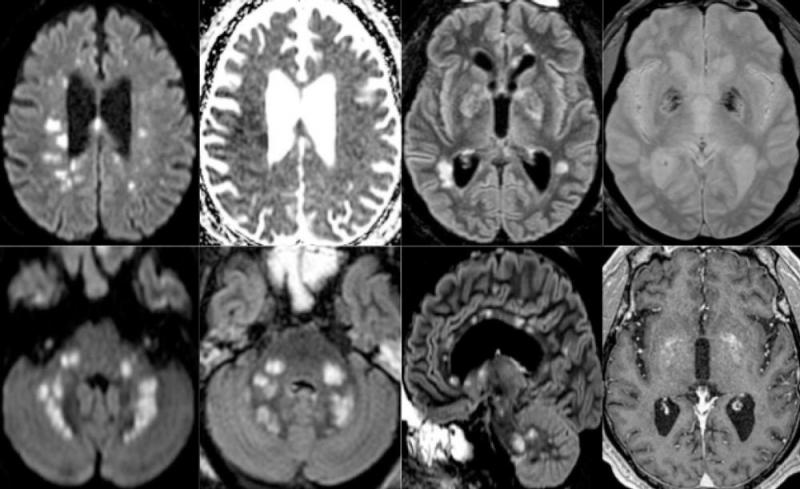

Among the 37 patients included, 28/37 (76%) were associated with one neuroimaging pattern, 7/37 (19%) with two patterns, and 2/37 (5%) showed three patterns. The most frequent MRI findings were: signal abnormalities located in the medial temporal lobe in 16/37 (43%) patients, non-confluent multifocal white matter hyperintense lesions on FLAIR and diffusion sequences, with variable enhancement, with associated hemorrhagic lesions in 11/37 patients (30%), and extensive and isolated white matter microhemorrhages in 9/37 patients (24%).

A majority of patients (20/37, 54%) had intracerebral hemorrhagic lesions and a more severe clinical presentation.

“Three main neuroradiological patterns could be distinguished, and the presence of hemorrhage was associated with worse clinical status. SARS-CoV-2 RNA was detected in the cerebrospinal fluid in only one patient, and the underlying mechanisms of brain involvement remain unclear,” the authors wrote. “Imaging and neurological follow up has to be undertaken in order to evaluate the prognosis of these patients.”